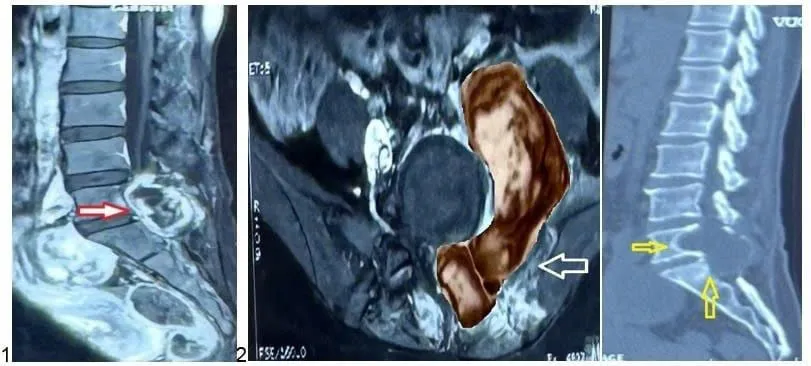

Kết quả chụp MRI tại Bệnh viện Nhân dân 115 cho thấy một khối u ác tính lớn dạng “hình quả tạ” ở vùng cột sống L5–S1, xâm lấn cơ cạnh sống, thân sống, cánh chậu và vùng phúc mạc.

Khối u ác tính vùng cột sống thắt lưng. Ảnh: BVCC

BS CKII Lê Điền Sơn, Phó trưởng khoa Ngoại Thần kinh – Bệnh viện Nhân dân 115, cho biết: “Khối u nằm đúng vị trí phẫu thuật cũ, có dấu hiệu phát triển bất thường, nghi ngờ tái phát và mang tính ác tính".